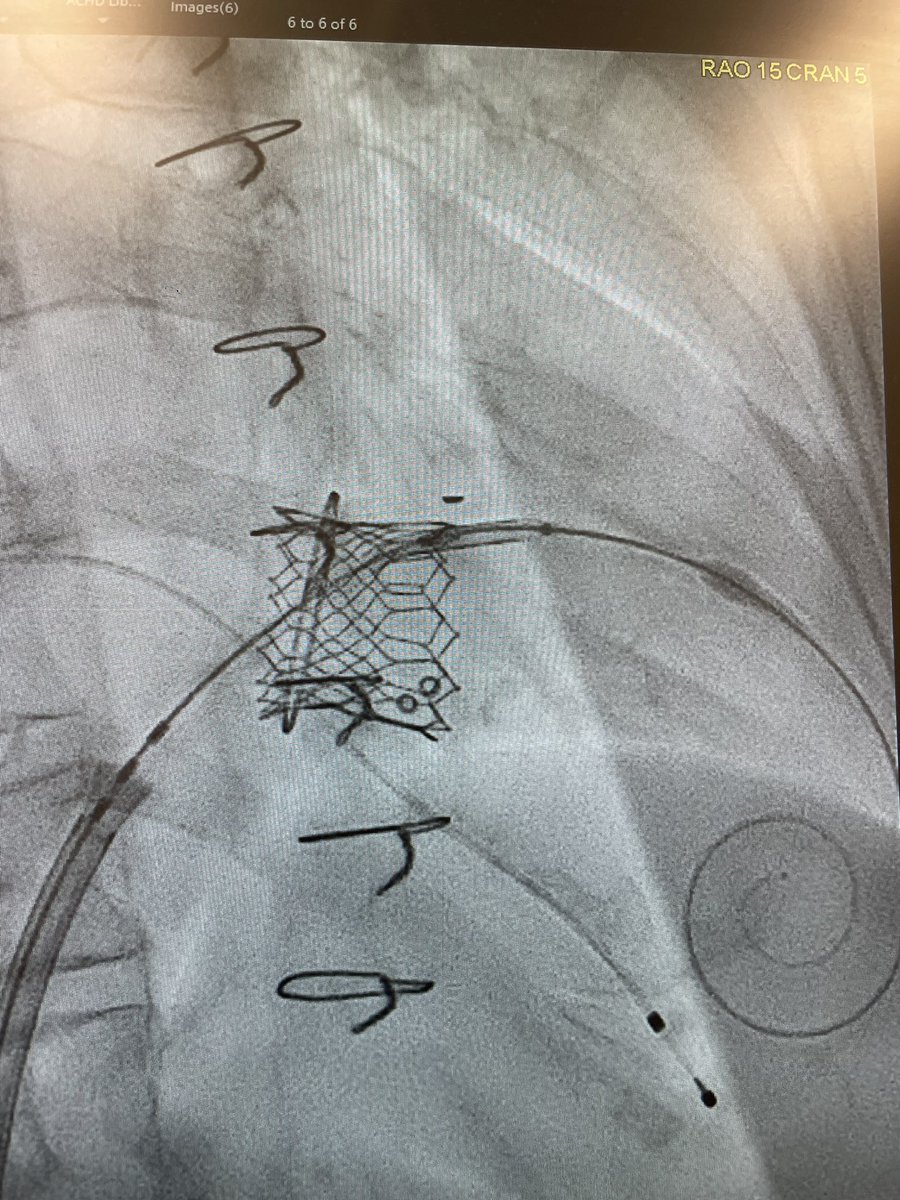

Exciting milestone at PSCC! We completed our first 6 cases using the Aterra Adaptive PreStent with the Sapien 29 valve for large RVOT. Proud to be the first in the region to adopt this innovation in structural heart care. We’ll share our experience @TCT_ME_